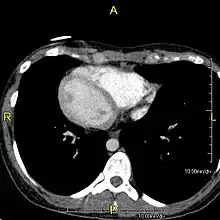

Axial CT image showing dextrocardia and situs inversus in a patient with Kartagener syndrome.

The condition affects all major structures within the thorax and abdomen. Generally, the organs are simply transposed through the sagittal plane. The heart is located on the right side of the thorax, the stomach and spleen on the right side of the abdomen and the liver and gall bladder on the left side. The heart's normal right atrium occurs on the left, and the left atrium is on the right. The lung anatomy is reversed and the left lung has three lobes while the right lung has two lobes. The intestines and other internal structures are also reversed from the normal, and the blood vessels, nerves, and lymphatics are also transposed.